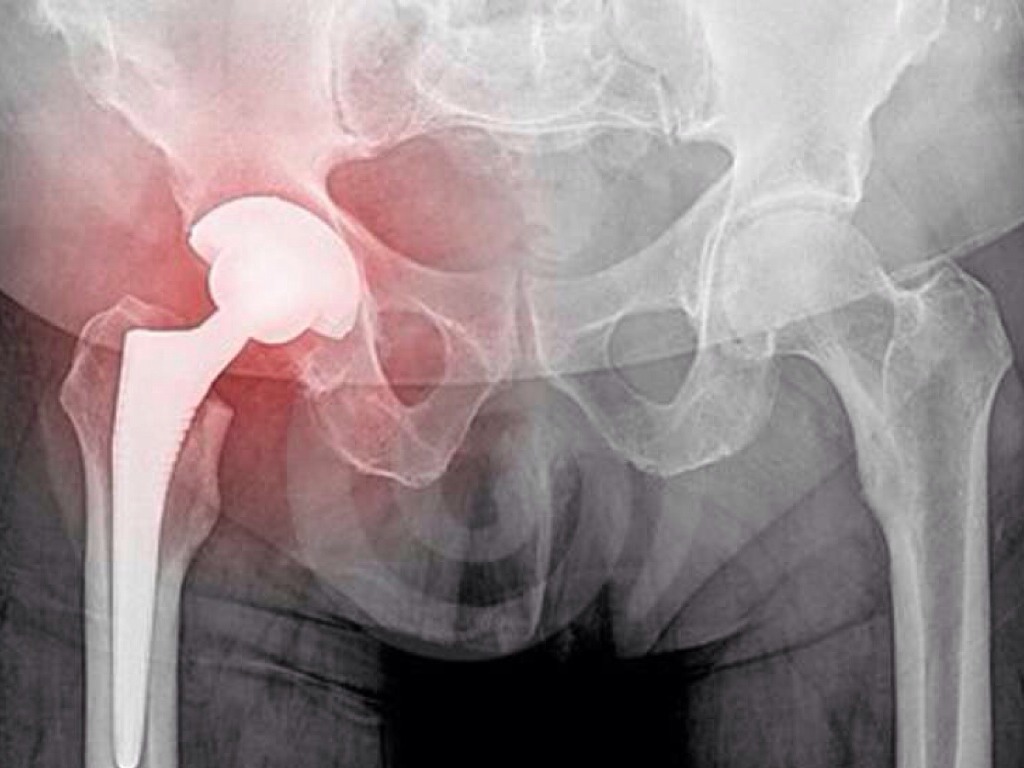

Man steals ring!